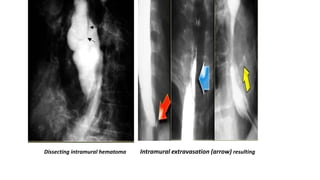

Esophageal hematoma:

These unusual lesions have been associated with increased

esophageal intraluminal pressure, most often vomiting,

instrumentation, and anticoagulation or bleeding disorders.

Some are spontaneous.

Blunt trauma is a rare cause.

Hematomas are self-limited and almost never progress to

perforation.

Most esophageal hematomas resolve in 1-2 weeks with

conservative treatment.

Dissecting intramural hematoma Intramural extravasation (arrow) resulting

Esophageal hematoma: These unusuallesions have been associated with increased esophageal intraluminal pressure, most often vomiting, instrumentation, and anticoagulation or bleeding disorders. Some are spontaneous. Blunt trauma is a rare cause. Hematomas are self-limited and almost never progress to perforation. Most esophageal hematomas resolve in 1-2 weeks with conservative treatment.

Dissecting intramural hematomaIntramural extravasation (arrow) resulting